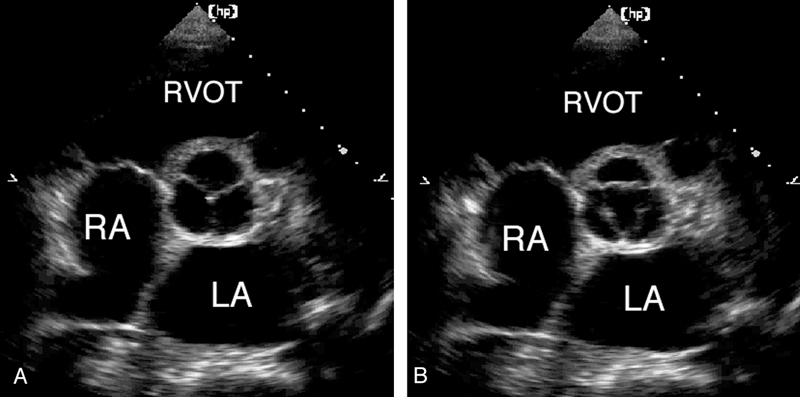

فحوصات تشخيصية لبعض امراض القلب والشرايين التاجية